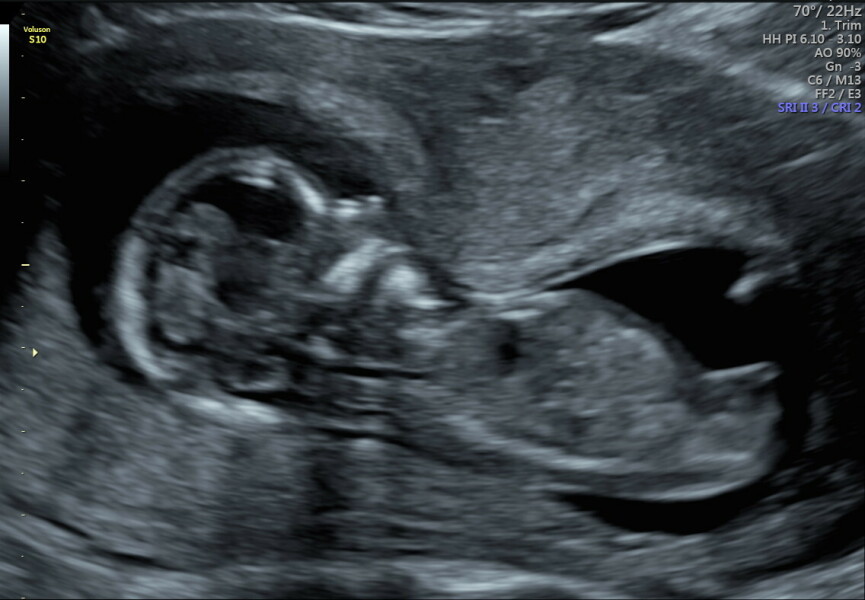

Well this is different. My friend did early glimpse for me and got this!

I have my scan in a week but I thought the same as you lot so it'll be interesting. I'll keep you all posted!

Leg or nub?

@Babyenroute thank you! I did that and they said girl too! I know it's just a theory and i can see how hard it is to tell but I look forward to next week's gender scan

Reddy01 · 25/07/2024 20:22

Thought I'd update with scan reveal today. They say baby girl! There are other pictures and I did worry beforehand that it may not be easy but there was no sign of any male parts! Thank you all for your guesses anyway. It is certainly not an easy thing to predict.